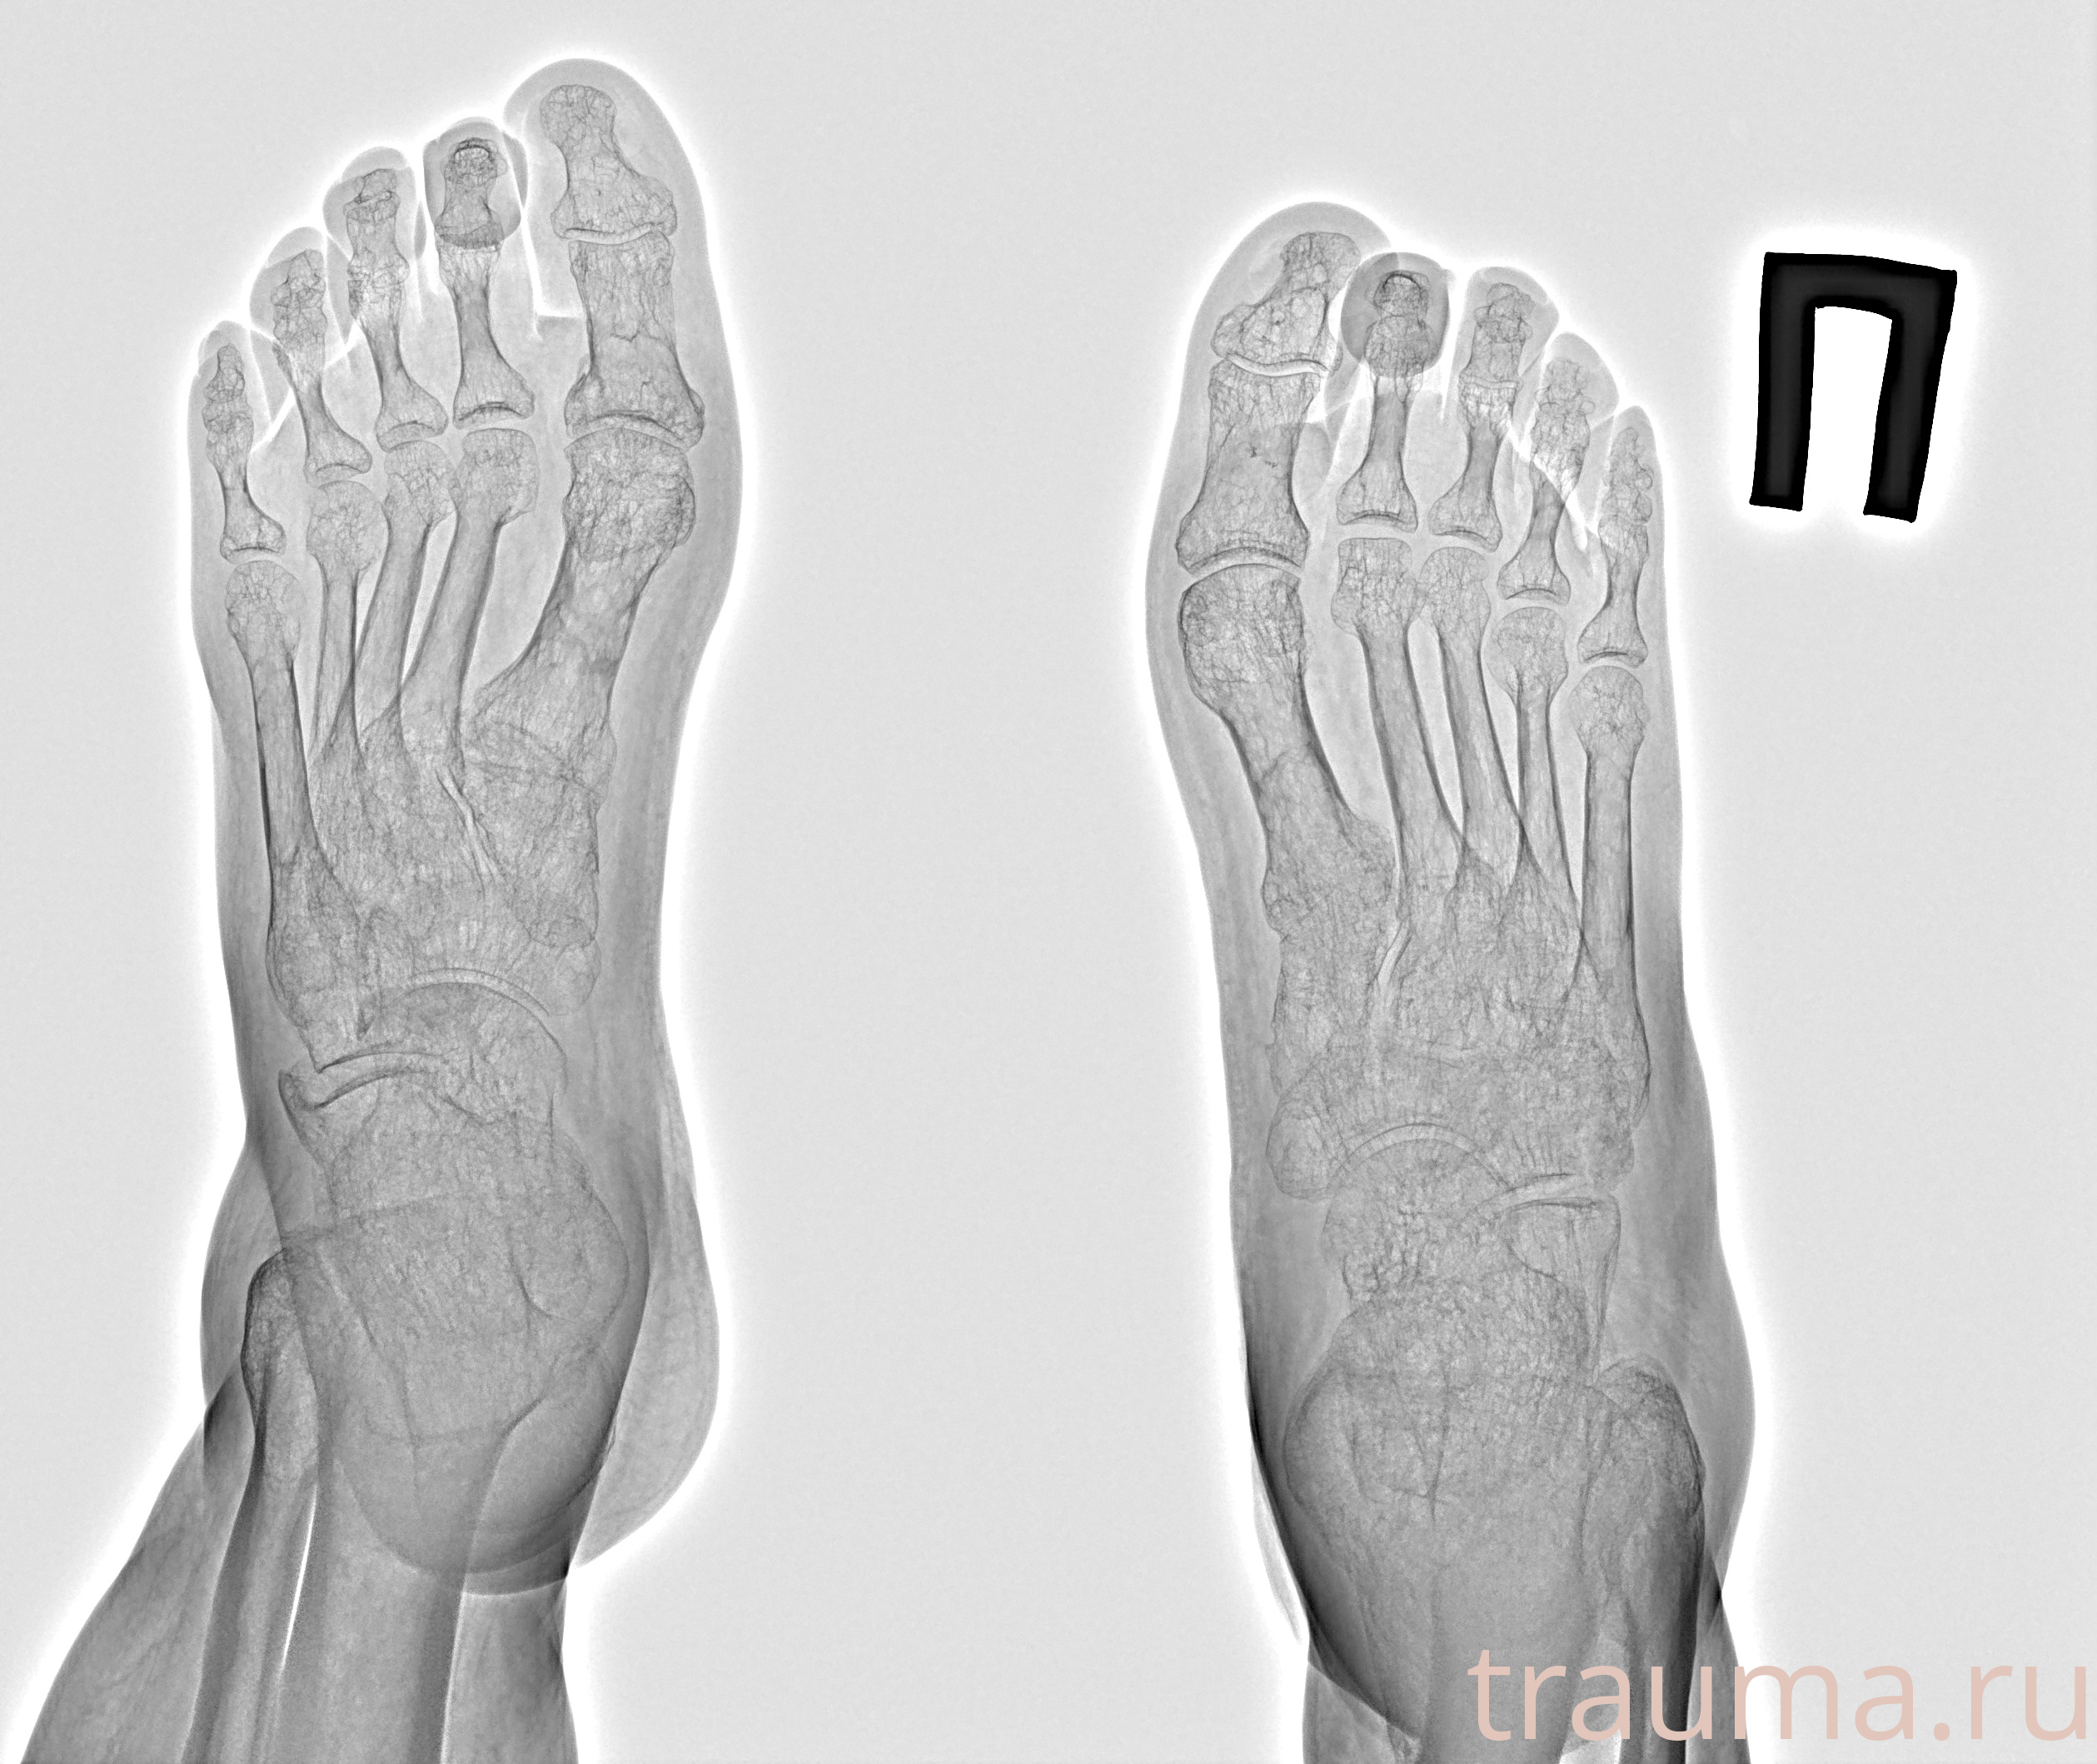

Рентгенограммы

Рентген на дому: по вашему адресу приезжает врач-рентгенолог, травматолог-ортопед с мобильным рентгеновским аппаратом, проводит диагностику травмы или заболевания, делает необходимые рентгенограммы, дает рекомендации по дальнейшему лечению. Получить качественные снимки в домашних условиях возможно благодаря уникальной методике, разработанной МосРентген Центром для института  Склифосовского